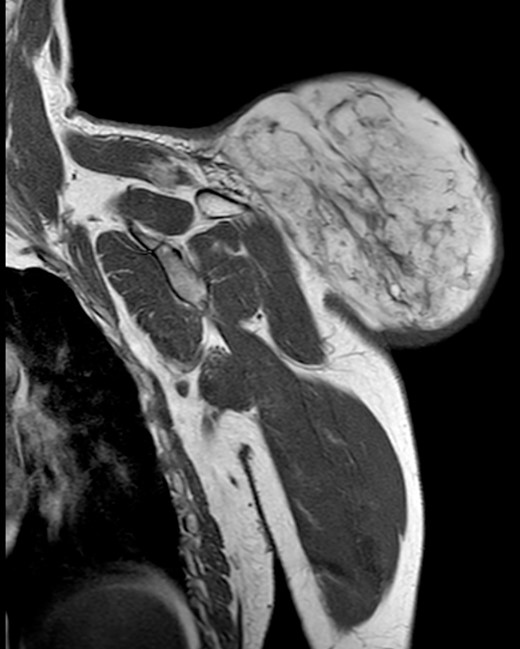

During the follow-up, a magnetic resonance (Figs 3 and 4) was performed describing a soft tissue lesion highly suggestive for liposarcoma as a first possibility diagnosis, with an addition image suggesting metastatic axillary lymph node. After the imaging results, biopsies were taken and analysed by the pathologist with a final diagnosis of PL.

Magnetic resonance imaging T2 with contrast: giant excrescent lesion of 19 × 18 × 14.4 cm of diameter located in the subcutaneous tissue of the posterior aspect of the scapula divided by multiple septums; axillary lymph node of ~0.9 cm; images compatible with liposarcoma with a metastatic axillary lymph node.

Magnetic resonance imaging T1: polylobulated lesion with multiple septa separating different areas of fat tissue.